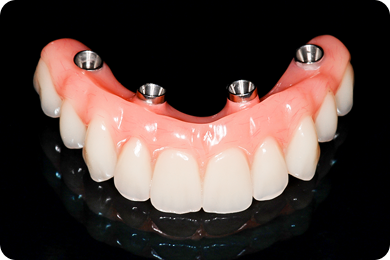

Зубы за 1 день от 7500₽ в месяц

с пожизненной гарантией

Установка

за 1 день